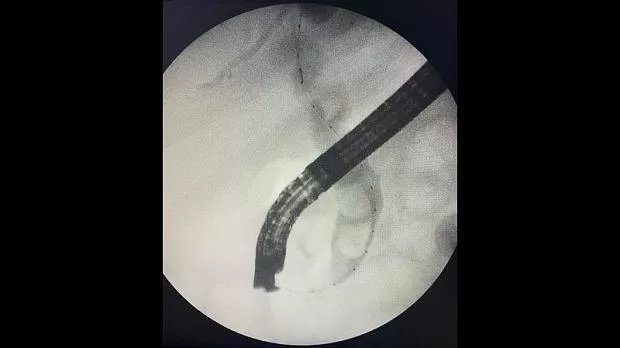

На следующий день произведена ретроградная холангиопанкреатография.

Отмечатся юкстапапиллярное расположение большого дуоденального сосочка тип-3. Канюляция папиллотомом pull-type ,контрастирование водорастворимым контрастом .

Рентгенологическая картина расширенния желчных протоков и наличие конкрментов в холедохе. Произведена эндоскопическая ограниченная папиллосфинктеротомия, отмечалось поступление темной желчи. Ревизия корзиной Дормия дали основания полагать ,что конкременты плотной консистенции.